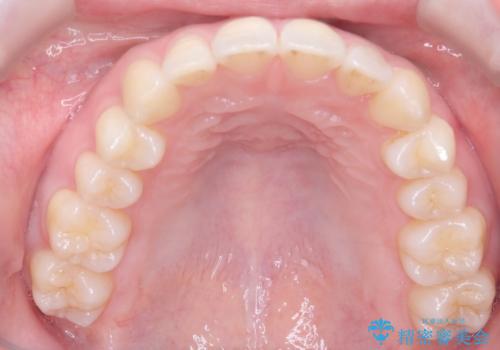

- 左上2の反対咬合(交叉咬合)をインビザラインを用いて治療しました。反対咬合は、歯列の不正咬合の一つであり、上の歯が下の歯よりも内側に位置する状態です。反対咬合は咀嚼や発音に影響を与えることがあります。

左上2の反対咬合をインビザラインで治療する際に、IPR(Interproximal Reduction)を行いました。 IPRとは、隣接する歯の間のエナメル質をわずかに削る手法で、歯の幅を減少させることによって歯列を整える技術です。